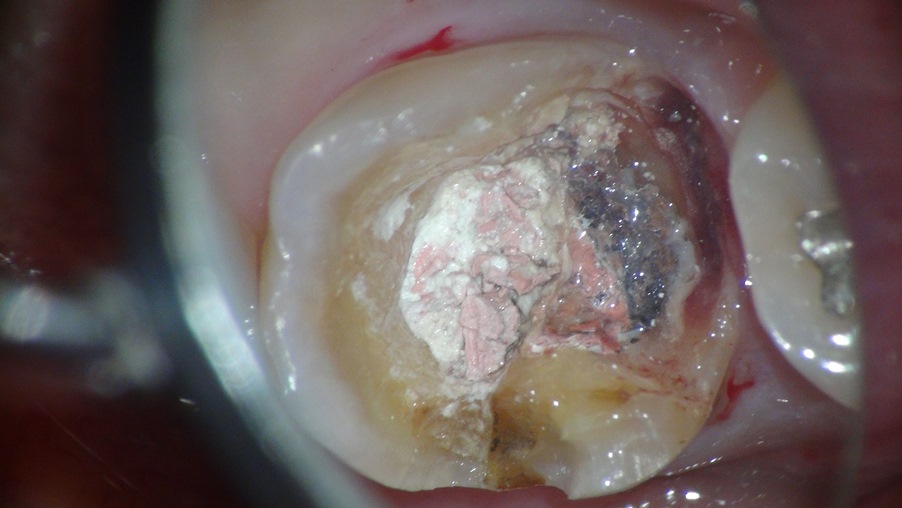

金属の冠を外すと中はかなり感染しておりました。

その部位を削合しながら窩洞の内面を整理し、歯を補強するとこんな感じ

そこから中に折れ残っている破折器具と格闘すると・・・・

おお~っと出てきました! 2本しっかり除去しまして

そんなに長くはないのですが、これが行く手を阻んでいました。